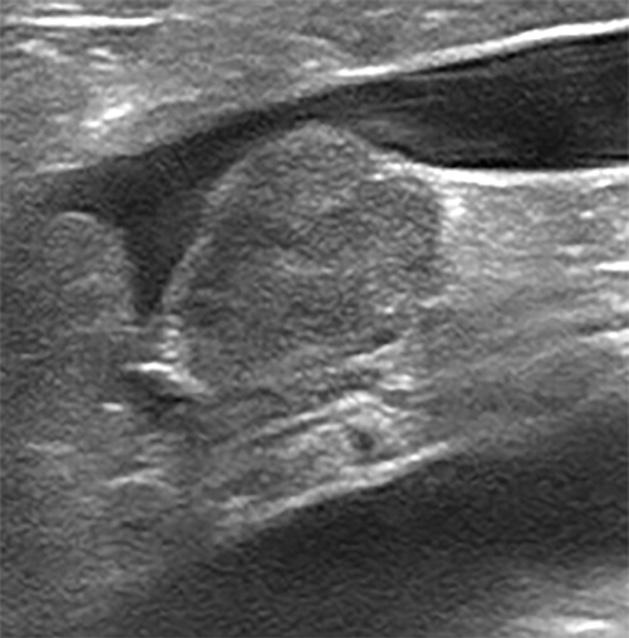

Se añaden dos dosis de hidralazina 0,5 mg/kg/BID por vía oral. Se realiza una ecografía completa y se aprecia: hipertrofia concéntrica de septo interventricular y pared libre ventricular izquierda, atrio izquierdo gravemente dilatado (ratio LA/Ao: 3,02), insuficiencia mitral de 7,5 m/s y disfunción diastólica grado III (imagen 3).